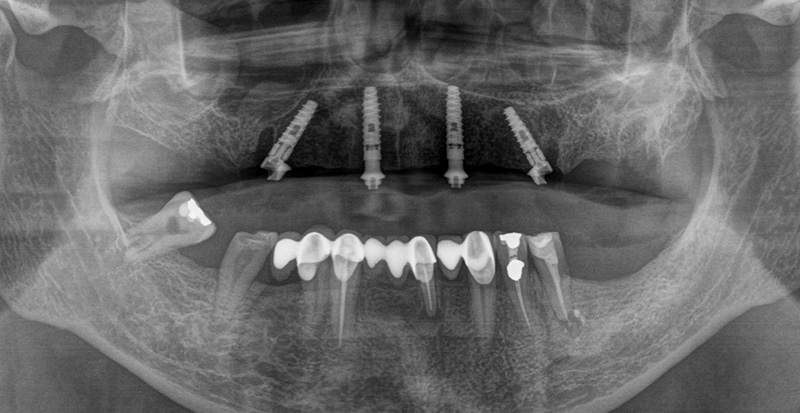

Après le retrait de l’ancien bridge métal-céramique, les dents restantes ont été extraites de manière atraumatique afin de préserver au maximum la paroi vestibulaire de l’os, ce qui est particulièrement important aux emplacements prévus pour la pose des implants. Quatre implants ont été posés immédiatement. Après la mise en place des piliers « multi-unit », une radiographie panoramique de contrôle a été réalisée avant la suture, afin de vérifier la position des implants ainsi que l’adaptation précise des piliers.

Fig. 03 : radiographie panoramique de contrôle a été réalisée avant la suture.